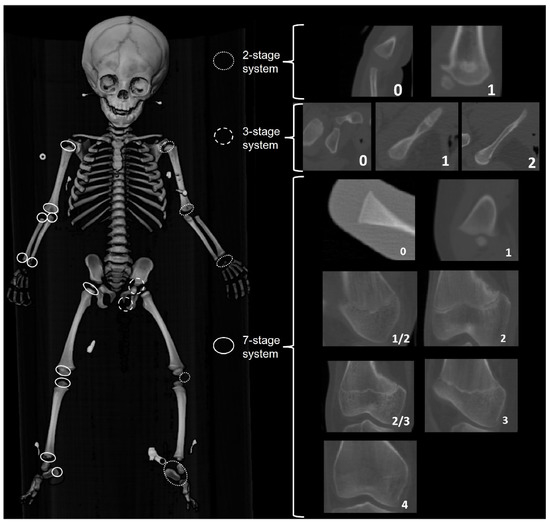

2.3.4. Epiphyseal Fusion (EF)

Epiphyseal fusion stages for proximal and distal long bone epiphyses, the calcaneal tuberosity, the ischiopubic ramus, the ilium and ischium, and ossification of the patella were recorded for both left and right-sided elements. Ossification of carpals and tarsals were scored binary absent (0)/present (1), and then the component score was recorded to indicate the number of elements present on either the left or right side. Three different staging systems were employed (Figure 8): a seven-stage system was used for the long bone epiphyses and the calcaneal tuberosity; a three-stage system was used for the pelvic epiphyses; and a binary absent/present was used for the carpals and tarsals, the ossification of the elements of the proximal and distal humerus (e.g., humeral head, lesser tubercle, greater tubercle, capitulum, trochlea, composite epiphyses), and the patella. Epiphyseal fusion was scored on CT slices for France, The Netherlands, Taiwan, and the United States samples, and on radiographs taken for the Angolan, Colombian, and South African samples.

Figure 8.

Three staging systems used to score the ossification of secondary centers, carpals, and tarsals (2-stage system) and epiphyseal fusion of the long bones and pelvis (7-stage system).